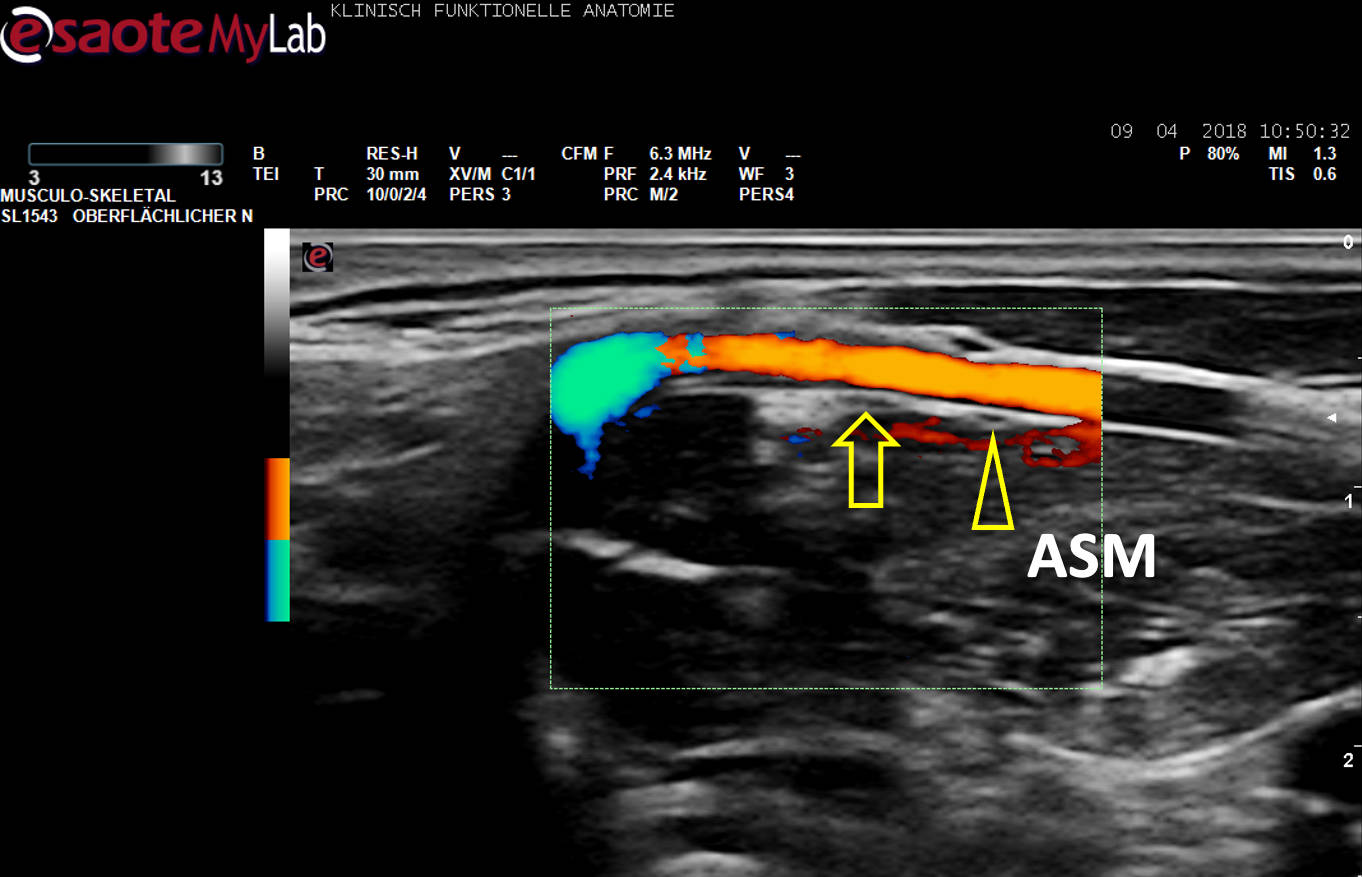

US-Darstellung eines N. phrenicus accessorius (Pfeilkopf) aus C5 auf dem M. scalenus anterior (ASM), ein Gefäß (Farbe) unterkreuzend. Pfeil: N. phrenicus aus C4.